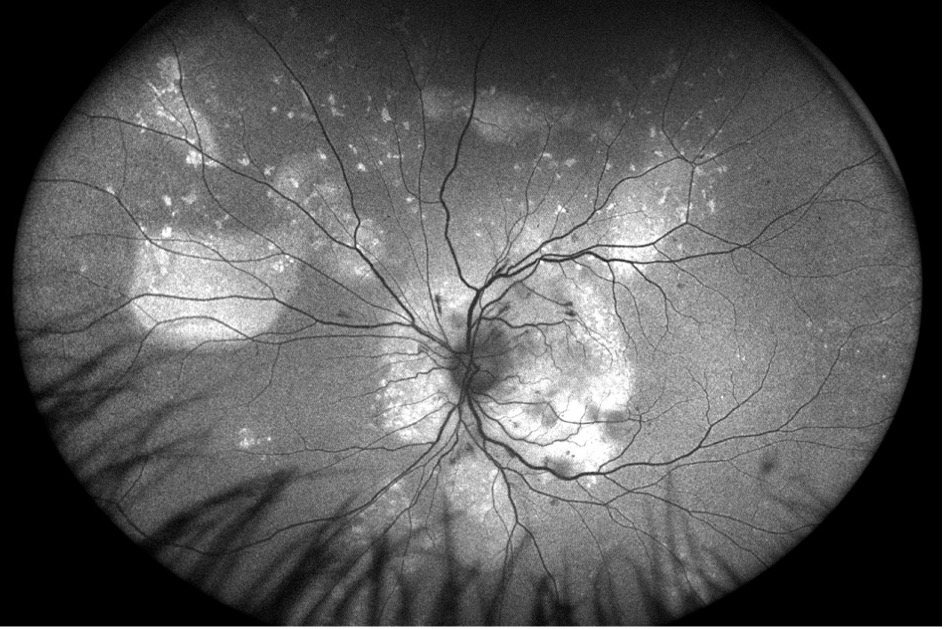

A 33-year-old Hispanic male was referred to Colorado Retina Associates with retinal hemorrhages and blurred vision, a concerning presentation for a generally healthy young man. His visual acuity was measured around 20/70 - 20/80 in both eyes. Fundus autofluorescence revealed similar findings in both eyes. In the left eye, the optic disc appeared slightly swollen with evident disc edema, along with vitreous exudates and swelling surrounded by cotton wool spots in the macula—microinfarcts of retinal tissue. The vessels displayed notable arteriovenous (AV) nicking, where the arteries compressed the veins at their crossing points. Autofluorescence also showed areas of hyperautofluorescence, correlating with localized exudative retinal detachments.

Ocular coherence tomography (OCT) images for both eyes revealed subretinal and intraretinal fluid, as well as hyperreflective material within the retina.

Given these findings, fluorescein angiography was ordered to explore a vascular cause. The imaging revealed retinal leakage in the macula and disc in the right eye, while the left eye showed more significant disc leakage along with spots of macular and retinal leakage.